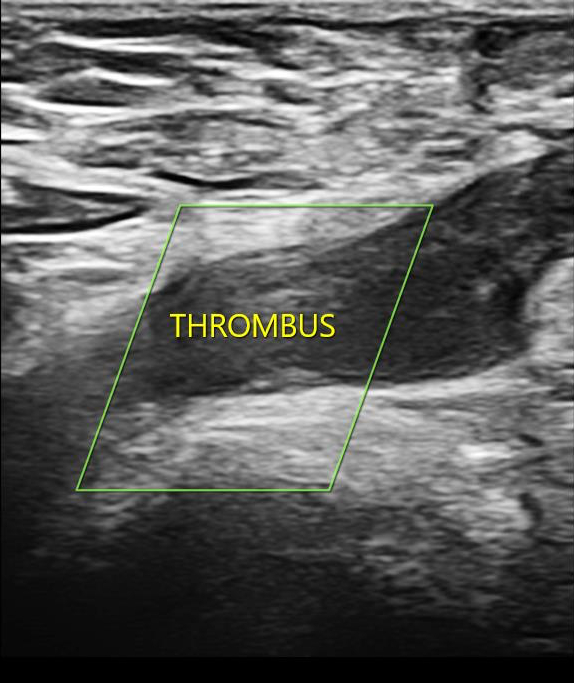

Description of Case: We present the case of a 33-year-old South Asian male who exhibited unilateral lower limb swelling and pain persisting for one month. Doppler ultrasonography revealed chronic deep vein thrombosis (DVT) affecting the left common femoral and deep femoral veins. The patient lacked identifiable risk factors for thrombosis, such as recent surgery, trauma, malignancy, or immobilization. Physical examination revealed signs of hypogonadism and gynecomastia. Hormonal assays indicated elevated gonadotropin levels with low serum testosterone levels, while karyotype analysis confirmed a 47,XXY genotype, consistent with KS. Further evaluations, including screening for acquired thrombophilias (antiphospholipid antibodies) and genetic mutations (Factor V Leiden, Prothrombin G20210A, and MTHFR C677T), yielded negative results. The patient was successfully managed with heparin, transitioned to long-term anticoagulation with warfarin, and demonstrated clinical improvement upon follow-up.